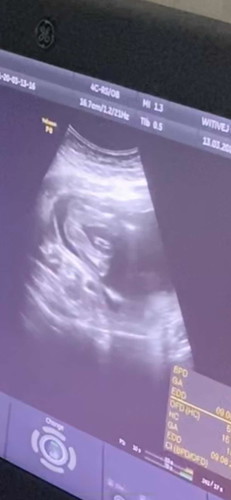

อยากได้ผช ค่ะมีโอกาศไหมค่ะ มีคัยเคยซาวแบบนี้แต่ได้ผช ไหมค่ะ คุณหมอบอก ญ 70-80% ค่ะ